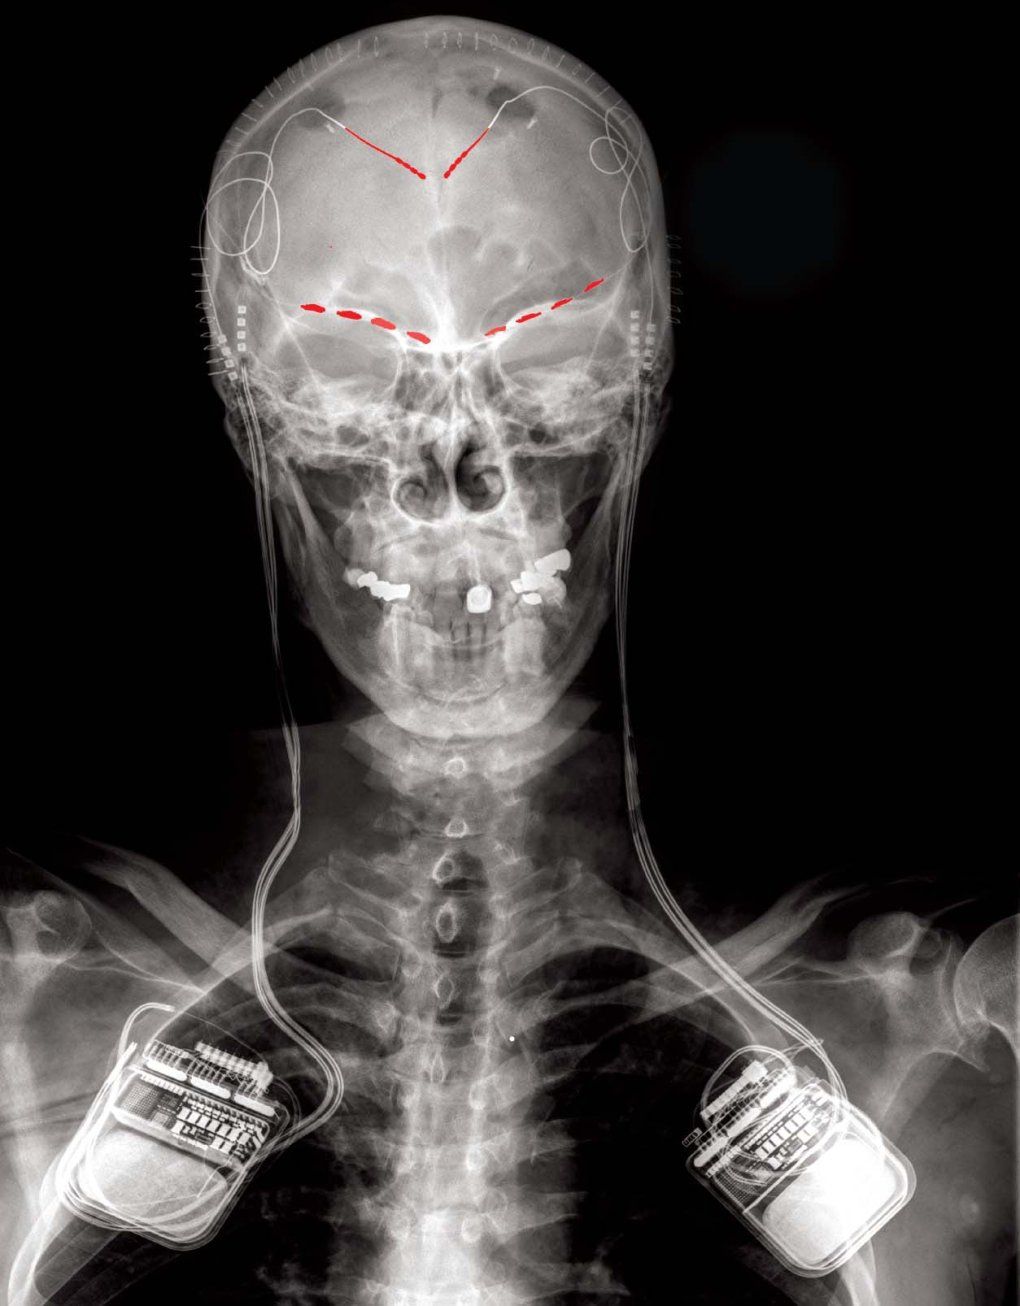

Deep brain stimulation delivers targeted electrical currents through tiny electrodes implanted in the brain. Like a cardiac pacemaker, these electrical pulses interrupt problematic brain activity - stopping tremors or pain signals before they take hold. While continuous deep brain stimulation has treated movement disorders like Parkinson's disease for decades, the technology often lagged behind patients' changing symptoms. And it hasn't been reliably effective when tested against other conditions.

Over the past decade, UCSF Neurological Surgery Professors Philip Starr , MD, PhD, and Edward Chang , MD, have pioneered surgical and brain mapping techniques, ushering in personalized deep brain stimulation. With this breakthrough approach, developed in part at UCSF, electrical stimulation is only delivered when the device detects abnormal brain activity associated with symptoms - activity that is unique to each patient.

Their next-generation of deep-brain stimulation technology responded to Connolly's Parkinson's symptoms in real time. The approach used an algorithm that recognized brain signals that indicate a symptom was developing and directed the device to deliver just the right amount of electrical stimulation to prevent it. Unlike the traditional deep brain stimulation of the early 2000s - which was always on - this new version only provides electricity when needed.

Connolly's treatment was made possible by years of NIH support for Starr and Chang, who pioneered the use of electrocorticography, a type of monitoring that allows researchers to record signals from inside the brain. The technology allowed Starr to implant the first multi-site recording device in a Parkinson's patient in 2013 , setting the stage for the next generation of "as-needed" personalized deep brain stimulation. UCSF researchers continue to fine-tune the technology by developing new ways to measure Parkinson-related walking changes , one of its most disruptive symptoms, to improve deep brain stimulation.